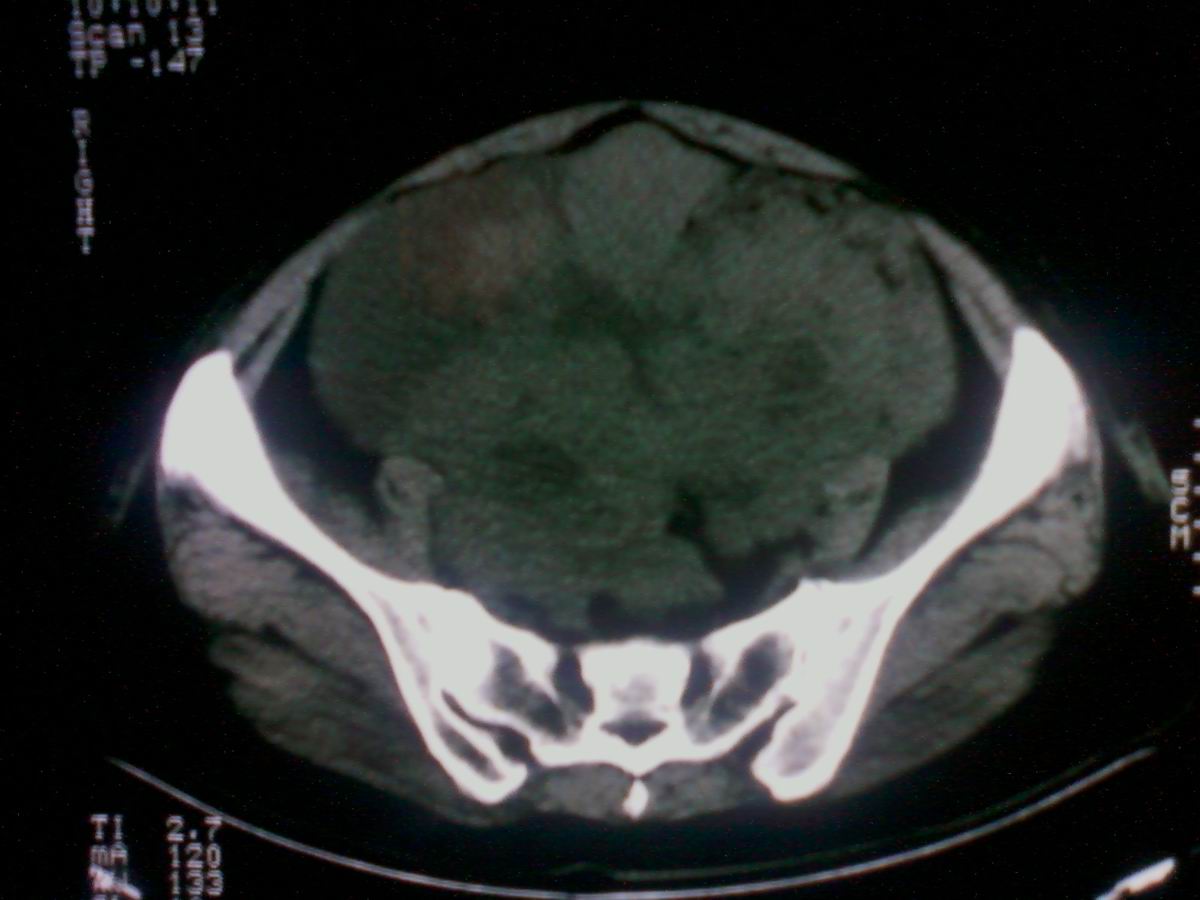

标题: CT25799:女性患者,45岁,腹胀,上腹部疼痛来诊,B超示盆腔 [打印本页]

标题: CT25799:女性患者,45岁,腹胀,上腹部疼痛来诊,B超示盆腔

考虑卵巢癌伴腹水

1)考虑卵巢恶性肿瘤。2)腹水。